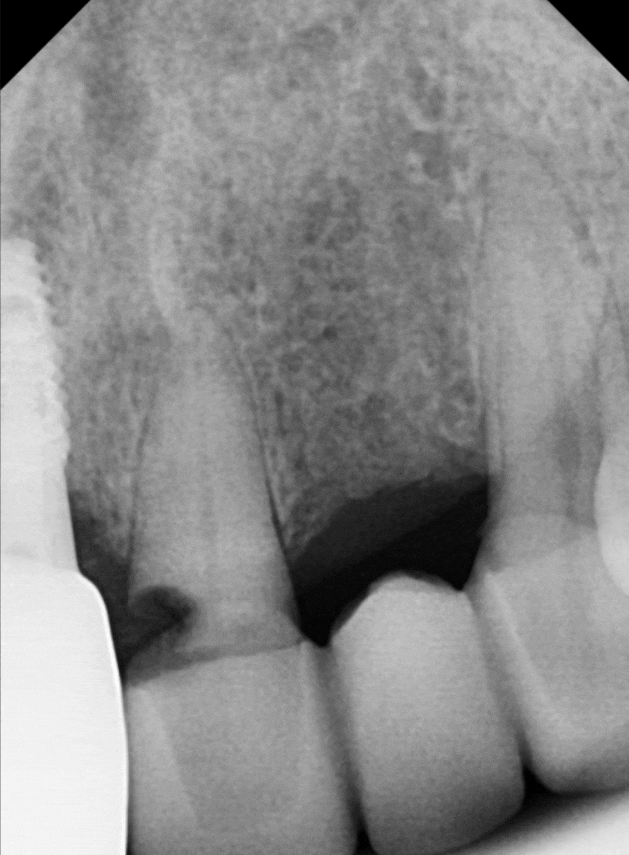

엑스레이로 확인해 보니

역시나 예상이 맞았습니다.

230516

앞니 옆면을 타고 뿌리 깊숙이

충치가 까맣게 진행 중이었습니다.

원인은 바로

'제거되지 않은 음식물'이었는데요.

브릿지 틈새에 낀 음식물이

빠지지 않고 안에서 부패하면서,

보철물 속의 치아를

야금야금 녹이고 있었던 겁니다.